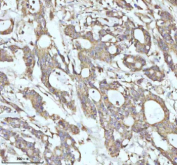

IHC (FFPE) : 0.5-1ug/ml

Amino acids 257-277 (NNHNFAKAREKVPKLHSIRDR-human) was used as the immunogen for this Caspase-8 antibody. This sequence is from the large subunit.